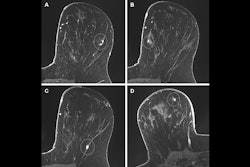

- Among those who received preoperative breast MRI, 51.5% were found to have additional suspicious lesions, and 69.1% of these patients underwent an image-guided biopsy.

- Patients who had a preoperative breast MRI exam underwent mastectomy more often than those who did not (49% compared with 31%, p < 0.001) but were less likely to require reexcision (8% compared with 14%, p < 0.001).